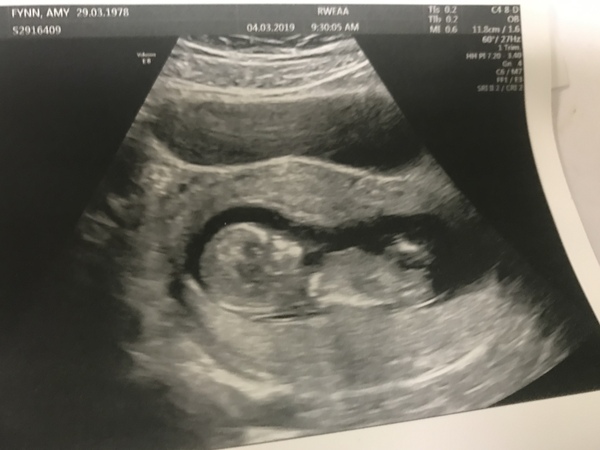

Was admitted to hospital on friday/Saturday due to hg and dehydration. They were unable to give me an IV due to my horrible veins. But on the bright side, i had a sneaky little ultrasound to check on baby! What a huge relief to know that there is a real baby in there and it's kicking away!

Super excited for tomorrow morning (proper dating scan). The quick scan on Friday put me four days ahead than i thought (so today im 12+6), so we'll see what tomorrow says!

Scan all good! Very wriggly but also wanted to lie on her tummy for most of the photos! So sonographer had some issues. Had to half empty bladder then fully empty and she still wouldn’t co-operate.

Measuring 12+4 now so gained 3 days based on lmp and 4 days from NIPT scan.